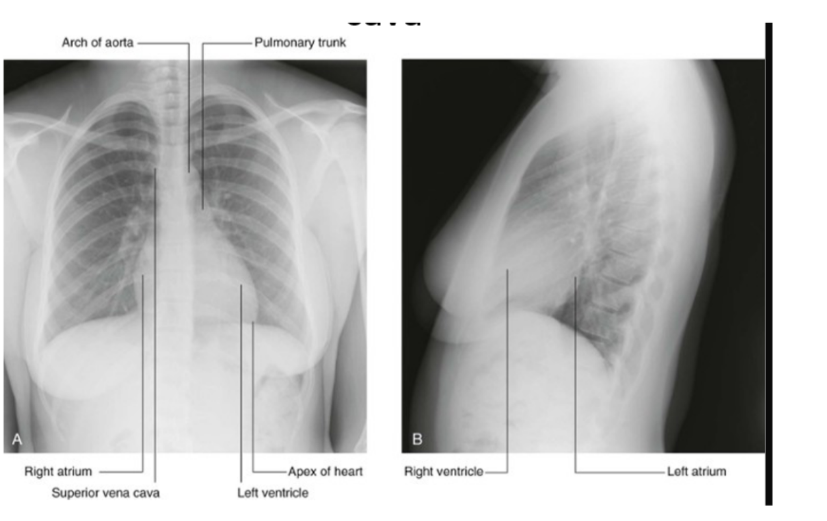

Superior vena cava

Begins posterior to the lower edge of the right first costal cartilage, where the right & left brachiocephalic veins join

Terminates at the lower edge of the right third costal cartilage, where it joins the right atrium

The lower half of it is within the pericardial sac (& thus in the middle mediastinum)

Superior vena cava receives the azygos vein immediately before entering the pericardial sac & may also receive pericardial & mediastinal veins

Can be easily visualized forming part of the right superolateral border of the mediastinum on a chest radiograph